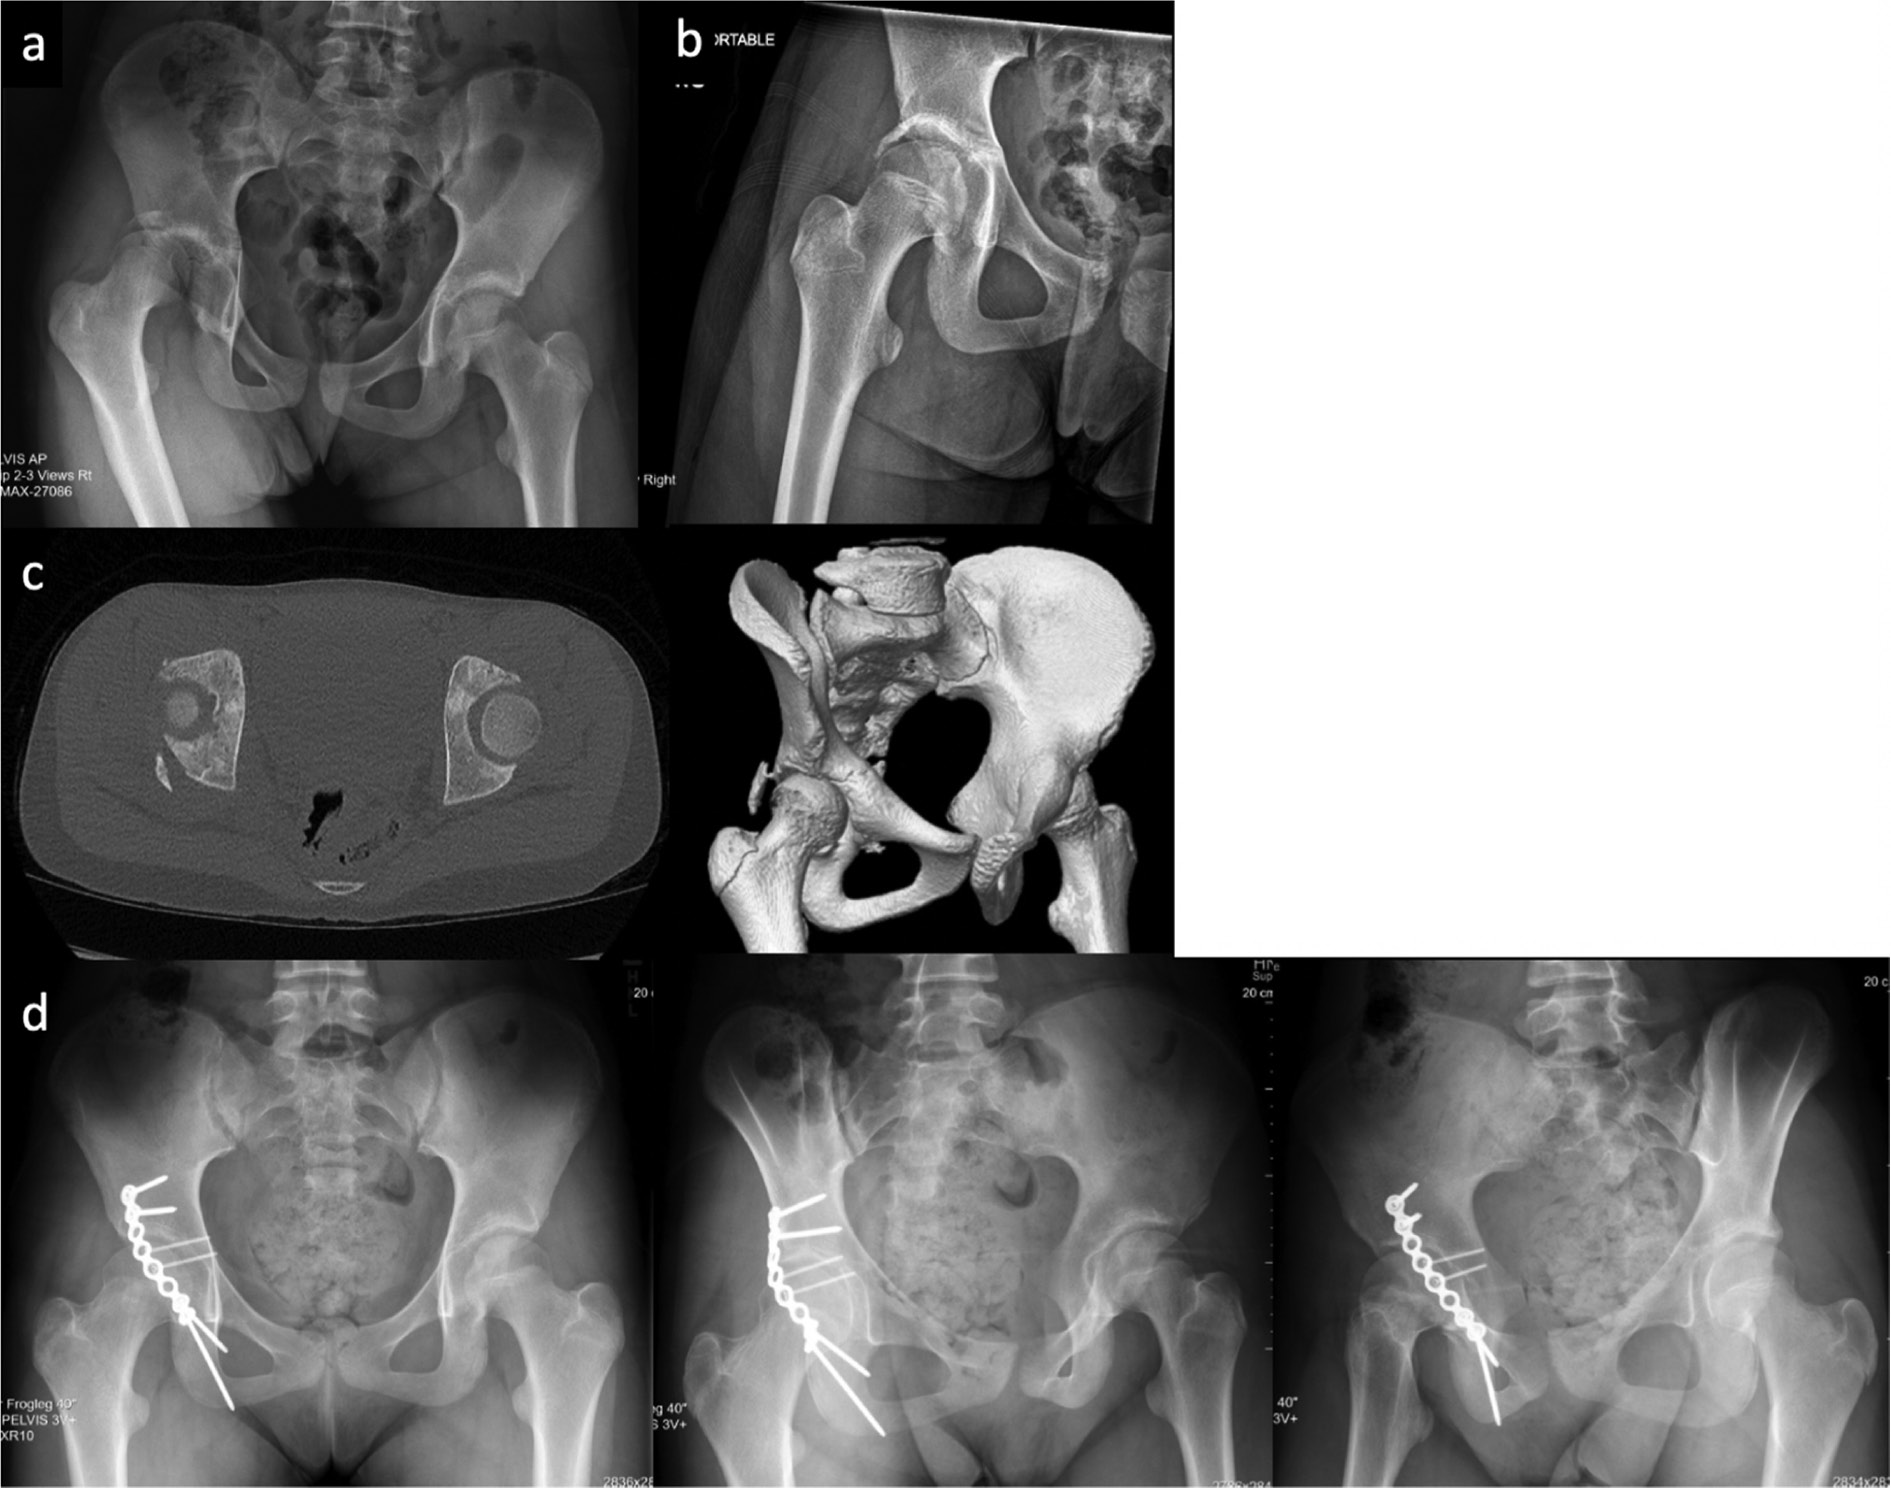

Figure 6. An 11-year-old female with low-energy right hip dislocation with posterior wall acetabulum fracture sustained during a basketball game. a. Initial injury AP pelvis radiograph, b. post-reduction radiograph, c. preoperative CT scan and 3D reconstructions demonstrating large displaced posterior wall acetabulum fracture, d. 1-year postoperative AP and Judet radiographs showing congruent hip joint without evidence of AVN.

jposna20220041_fig6.jpg

Case example: An 11-year-old female basketball player was running and cutting in a game when she had a misstep and sustained a low-energy right hip fracture dislocation (Figure 6). Initially seen at a local emergency room, she underwent a closed reduction of her dislocation within 6 hours and then was transferred to a pediatric tertiary care center for further management. She had a displaced posterior wall acetabulum fracture and underwent open reduction internal fixation through a posterior approach. Postoperatively, she was kept toe-touch weight-bearing for 8 weeks and then was allowed to progress to activities as tolerated after 12 weeks. After 1 year, the patient had returned to sport without pain and had no evidence of AVN on radiographs.